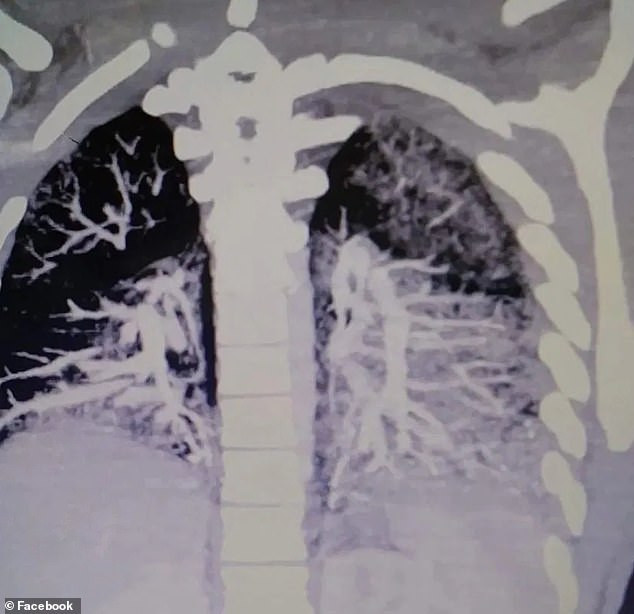

Anthony Mayo, din Pennsylvania, a ajuns la spital în stare gravă, săptămâna trecută, pentru că nu a mai putut să respire din cauză că plămânii săi erau plini cu ulei solidificat, provenit de la dispozitivele de vaping, potrivit Metro.

Tatăl băiatului a spus că medicii l-au avertizat că plămânii adolescentului arată "ca cei ai unei persoane de 60 de ani care fumează două pachete de țigări pe zi" și este probabil ca starea să nu se mai îmbunătățească vreodată.

"Spunea că e ceva la modă și care nu îți face rău. Sunt la fel de vinovat, pentru că am acceptat. Nici nu i-am dat voie, dar nici nu l-am oprit", a spus tatăl băiatului Keith Mayo, care a si publicat pe Facebook imaginile cu radiografia plămânilor băiatului.